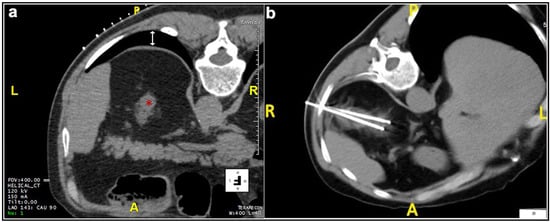

Most patients (87.4%) were treated prone. Twenty patients were treated in the oblique or lateral decubitus position (Figure 1). Only two treatments were carried out with the patient supine. Local anesthesia was mostly sufficient for the large majority of the procedures and mild conscious sedation was administered if needed. One patient required general anesthesia for the impossibility to collaborate with breath holds during the procedure because of dementia. In most cases, one lesion was treated in each procedure. In five patients, two lesions were treated in the same procedure, and, in another two patients, three lesions and four lesions were treated in a unique procedure, respectively. A median of two cryoprobes were used for each intervention (range: 1–8). Eight cryoprobes were required for the treatment of one of the largest tumors (5.4 cm), which revealed to be a clear-cell carcinoma at biopsy. The procedure was technically successful, and no complications occurred. Eighty-nine lesions required a complex cryoprobe approach. Hydro-dissection was necessary for the treatment of 13 tumors due to the vicinity of the bowel that could not be displaced after changing the position of the patient (Figure 2). In two cases, emptying of a cyst adjacent to the lesion was deemed necessary. Only one patient required a trans-hepatic approach (Figure 3). The procedures had a median duration time of 84 min (range: 40–153). Data on radiation exposure was available for 113 out of 138 patients with a median radiation exposure of 43.7 mSv.

Figure 2. Male, 75 years old. Hydrodissection technique. (a) At the initial scan, the distance between the lesion (*) and an intestinal loop was 3.76 mm, significantly inferior to the safety margin of 1 cm required. (b) A 16G needle cannula (green arrow) was inserted for the injection of sterile water to increase the distance between the structures. The lesion was adequately treated with three cryoprobes (orange arrow). (c,d): Coronal plane and 3D reconstruction images, respectively.